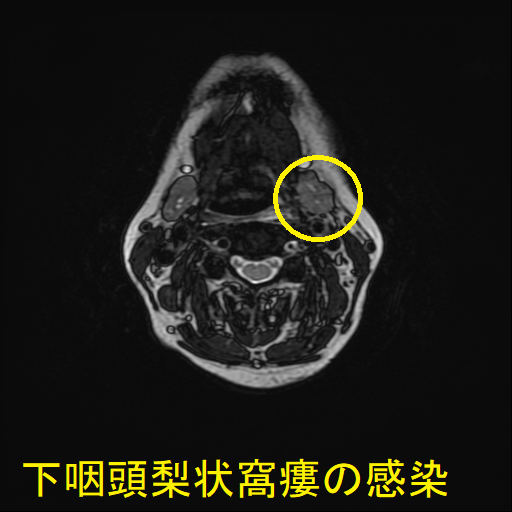

- 通常の造影頸部CTで、甲状腺外の膿瘍形成と、その範囲が明らかになります。

- 下咽頭部造影CTで、下咽頭梨状窩瘻を見つけます。

急性化膿性甲状腺炎に至らない下咽頭梨状窩瘻の感染もあります。下咽頭梨状窩瘻が甲状腺内でなく、甲状腺周囲に開口している場合に起こります。

![下咽頭梨状窩瘻の感染 (水平断)[拡大] 下咽頭梨状窩瘻の感染 (水平断)[拡大]](../images/basic/basic5/images20251109162258.png)